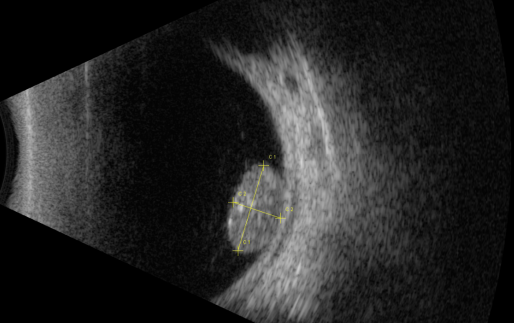

視網(wǎng)膜母細(xì)胞瘤的分類和治療

視網(wǎng)膜母細(xì)胞瘤是嬰幼兒常見(jiàn)的眼內(nèi)惡性腫瘤,可危害患者的視力、眼球和生命。其惡性程度高,多發(fā)于兒童,尤其是3歲以下的兒童,常表現(xiàn)為白瞳癥,可侵及單眼或雙眼。

視網(wǎng)膜母細(xì)胞瘤分類

根據(jù)腫瘤的表現(xiàn)和發(fā)展過(guò)程可分為眼內(nèi)期、青光眼期、眼外期和全身轉(zhuǎn)移期。

開(kāi)始在眼內(nèi)生長(zhǎng)時(shí)外眼正常,因患兒年齡小,不能自述有無(wú)視力障礙,因此本病早期一般不易被家長(zhǎng)發(fā)現(xiàn)。當(dāng)腫瘤增殖突入玻璃體或接近晶體時(shí),瞳孔區(qū)出現(xiàn)黃白色反光,如貓眼樣(“黑貓眼”),此時(shí)常因視力障礙而瞳孔散大、白瞳癥或斜視被家長(zhǎng)發(fā)現(xiàn)。